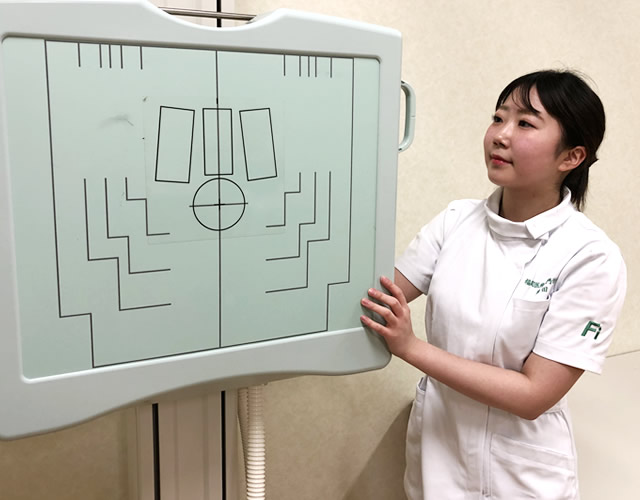

MRIは磁場を利用した診断装置で、体の任意の断面画像を撮影することが可能です。現代医療においては、欠かすことの出来ない高度医療機器のひとつになっています。今回の実習では臨床の場を想定してMRIの撮影を学生自ら行いました。学生は装置の準備や撮影条件の設定、撮影部位の位置合わせなどに関して担当教員より指導を受けながら撮影を進めていきます。また、患者さんへの検査の説明や検査機器への誘導などの接遇も実習課題となっています。

診療画像検査学実習風景

今回の実習時間は90分です。撮影実習は少人数(5名)のグループに分かれて行われます。実習を始める前に先生より実習内容に関して説明を受けているところです。今日の撮影部位は膝(ひざ)に決まりました。

患者さん役(学生)を撮影室に呼び入れる前に装置のセッティングを行っています。女子3名で準備は完了しました。

![]()

診療放射線技師は医療機器を扱うため機器に関しての知識を学ぶことは大事なことですが、人と人とのつながり(接遇)も非常に大事なことであることも教えています。患者さんに対してこれから行う検査の内容をしっかりと説明することは、診療放射線技師の大切な仕事になります。